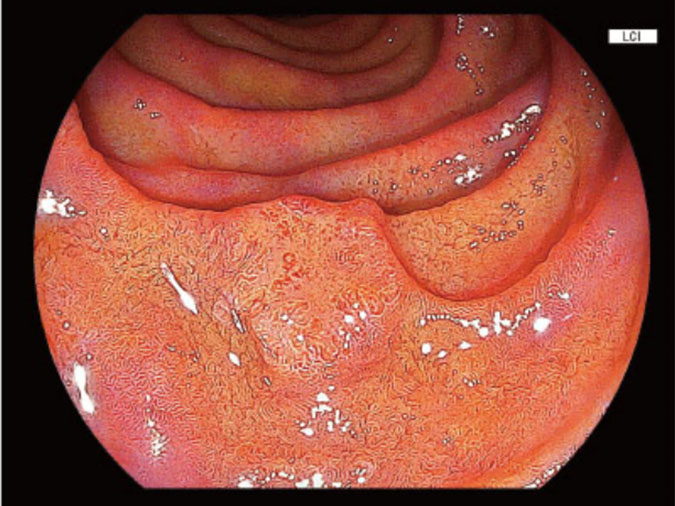

当院で使用しているFUJIFILM内視鏡では、NBIと同様に病変を見つけやすくする技術としてBLI、LCIという観察モードを使用しています。

LCI(Linked Color Imaging)とはLCIは、粘膜のわずかな色の違いを強調する技術です。炎症や早期がんは、周囲の粘膜とわずかに色が異なることがあります。LCIを使用するとその色の違いが強調され、病変の見逃しを減らすことが期待できます。

特に

などの発見に役立ちます。